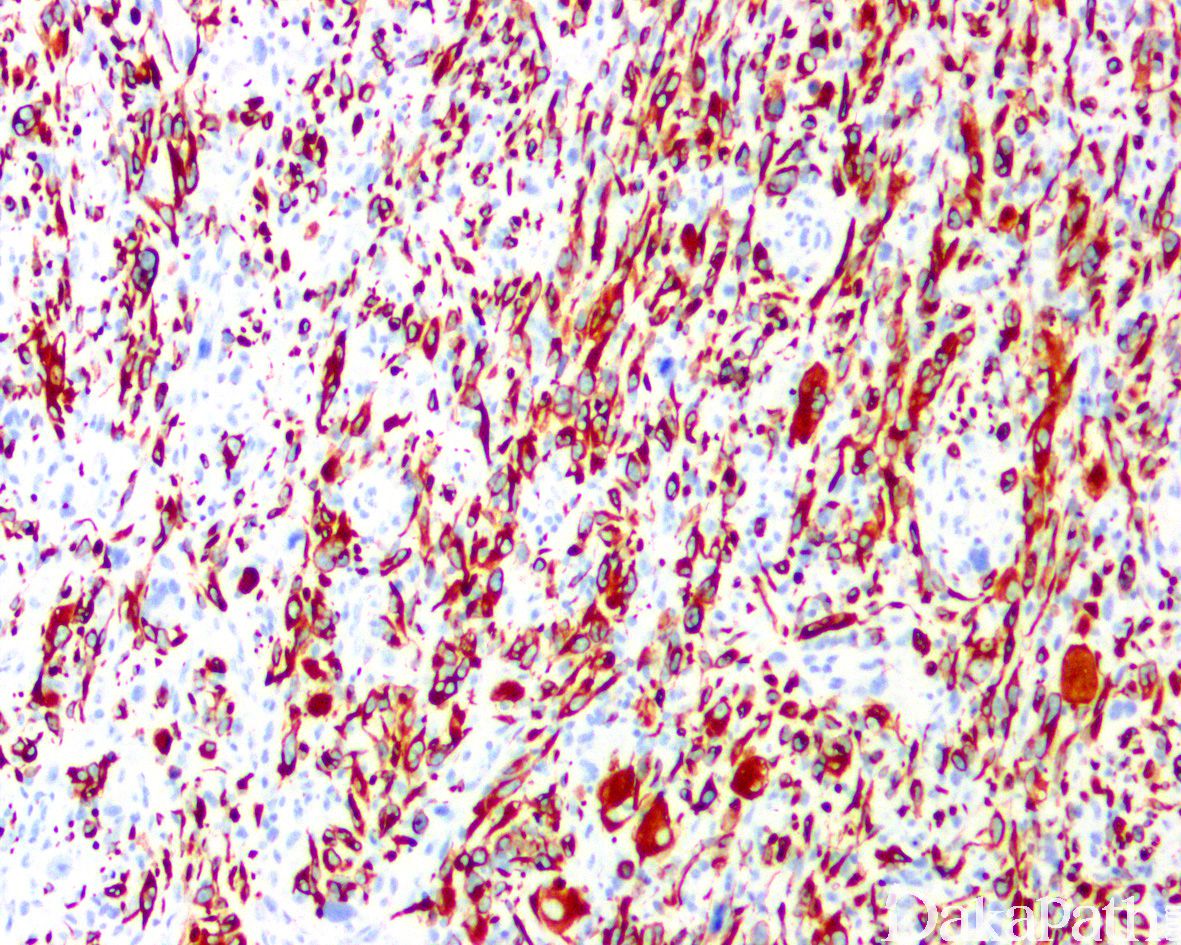

免疫组织化学染色:

desmin 弥漫阳性,SMA、MyoD1 和 myogenin 阳性(有时可能很局灶),CK、S100. CD34 一般为阴性。